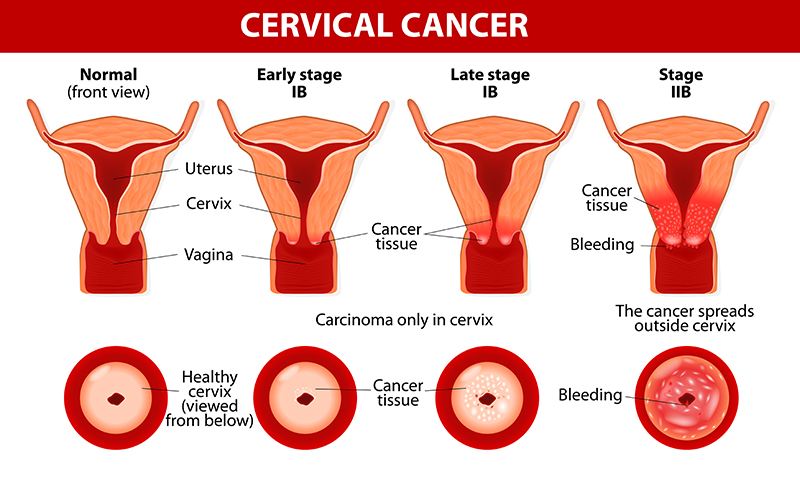

You may strengthen the body's immune system and quite simply create resistance to an hpv infection in basically just a few months, prior to the time that it could originate any important. Ad all cervical cancer treatments are not the same is what you've tried not working? Learn about the stages of cervical cancer and what they mean.